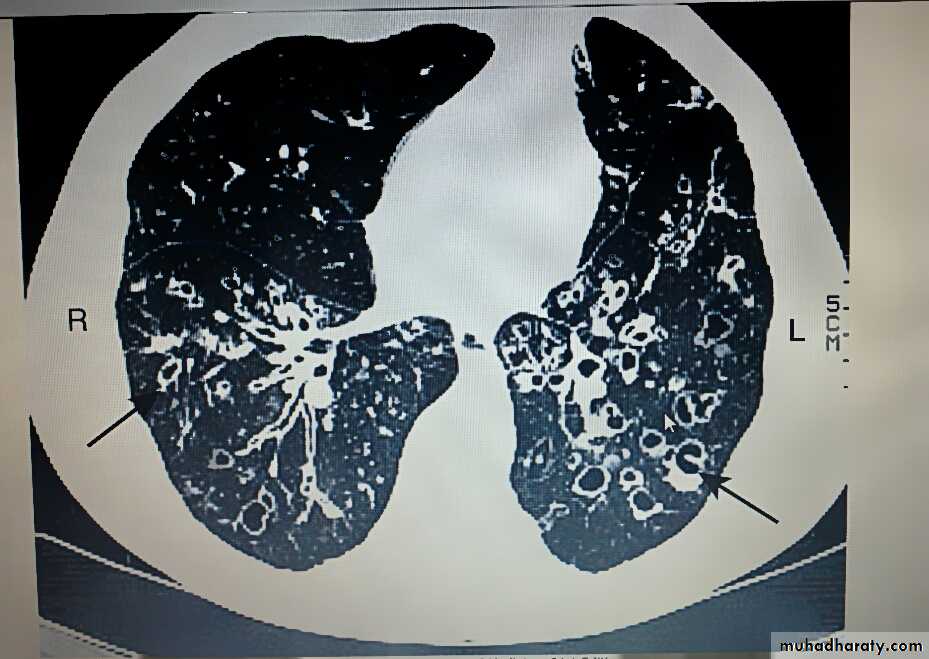

Bronchiectasis

Bronchiectasis means abnormal dilatation of the bronchi.Chronic suppurative airway infection with sputum production, progressive scarring and lung damage are present, whatever the cause.

The bronchiectatic cavities may be lined by granulation tissue, squamous epithelium or normal ciliated epithelium.

Chronic inflammatory and fibrotic changes are usually found in the surrounding lung tissue, resulting in progressive destruction of the normal lung architecture in advanced case